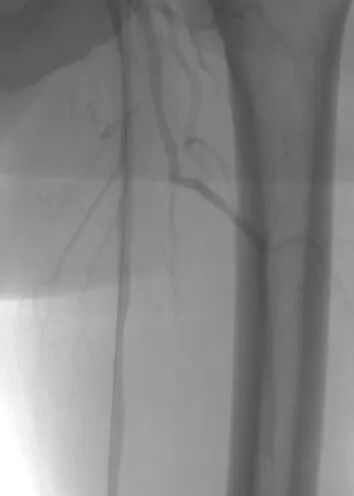

术中抽栓正是基于这一精准诊断,团队迅速调整治疗策略,采用Straub-Rotarex血栓切除系统实施精准抽栓治疗。该系统如同血管内的“吸尘器”,能够将血栓碎屑彻底吸出,无需植入支架。

术后患者下肢静息痛即刻消失,血管血流恢复通畅。这一治疗既规避了盲目植入支架可能引发的远期再狭窄风险,也真正做到了“因病施治、精准施策”。